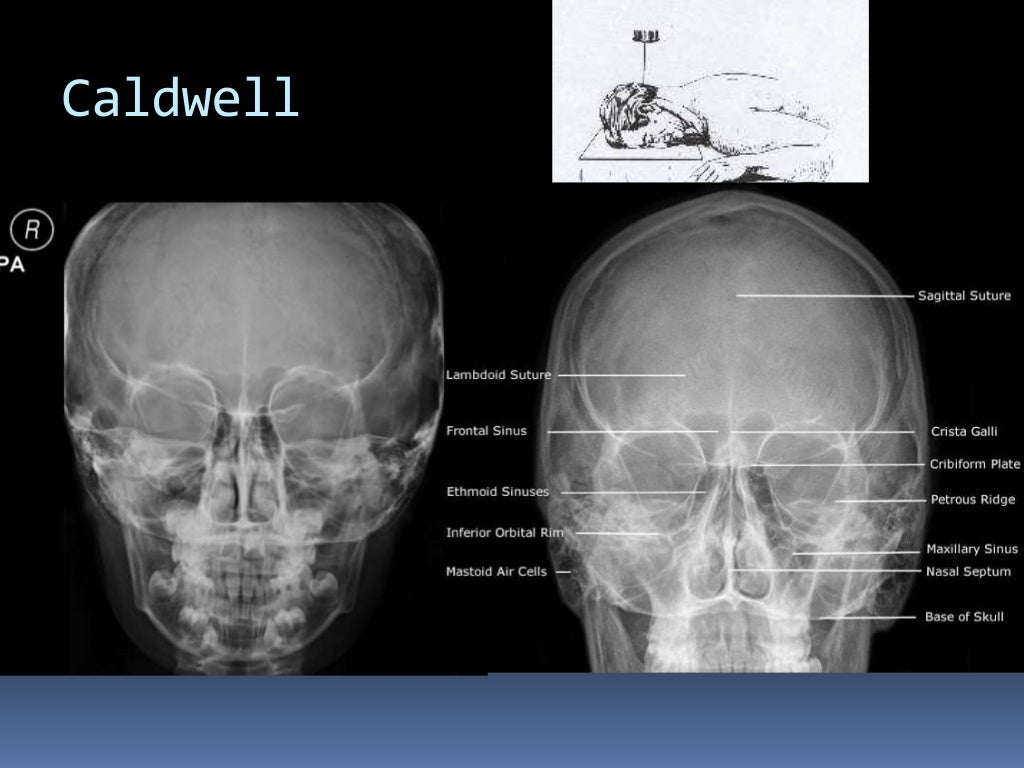

Download scientific diagram | Proyección de Waters: aumento de densidad de partes blandas de los senos maxilares (estrella) y presencia de masa en la faringe (flecha). from publication: Pólipo.. Citation, DOI, disclosures and article data. The Caldwell view is a caudally angled radiograph, with its posteroanterior projection allowing for minimal radiation to the orbits. This view may be used in imaging of the skull or facial bones depending on the clinical indications.

Proyección de Caldwell Wikiwand

RADIO ANATOMIA CRANEO

Incidencias de CADWELL y WATERS NeuroMedicine uDocz

Descarga RX – Posiciones Radiológicas: https://play.google.com/store/apps/details?id=com.Tarter.RXPosicionesRadiolgicas&pcampaignid=web_sharehttps://apps.app.. Study with Quizlet and memorize flashcards containing terms like Proyección de Caldwell también llamada., Proyección de Waters también llamada., ¿Qué estructuras se aprecian mejor con la proyección de Caldwell? and more.